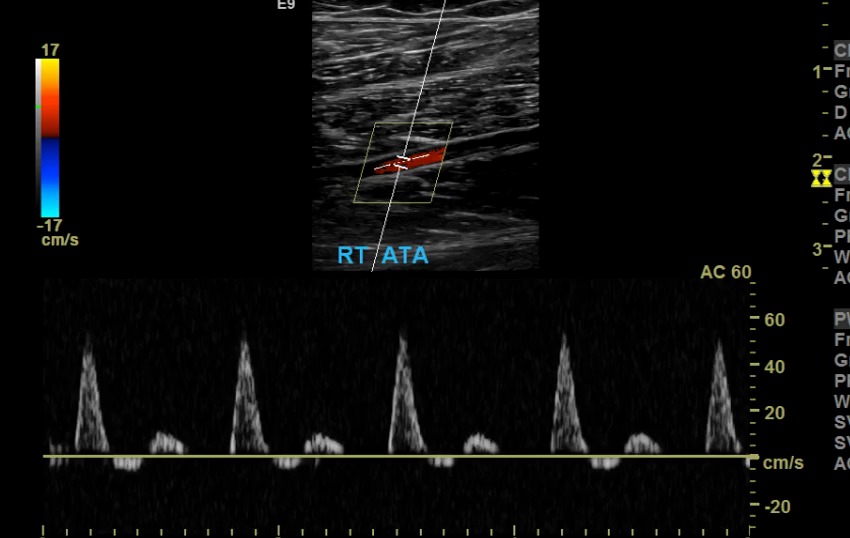

Scale/PRF too high

PRF too high